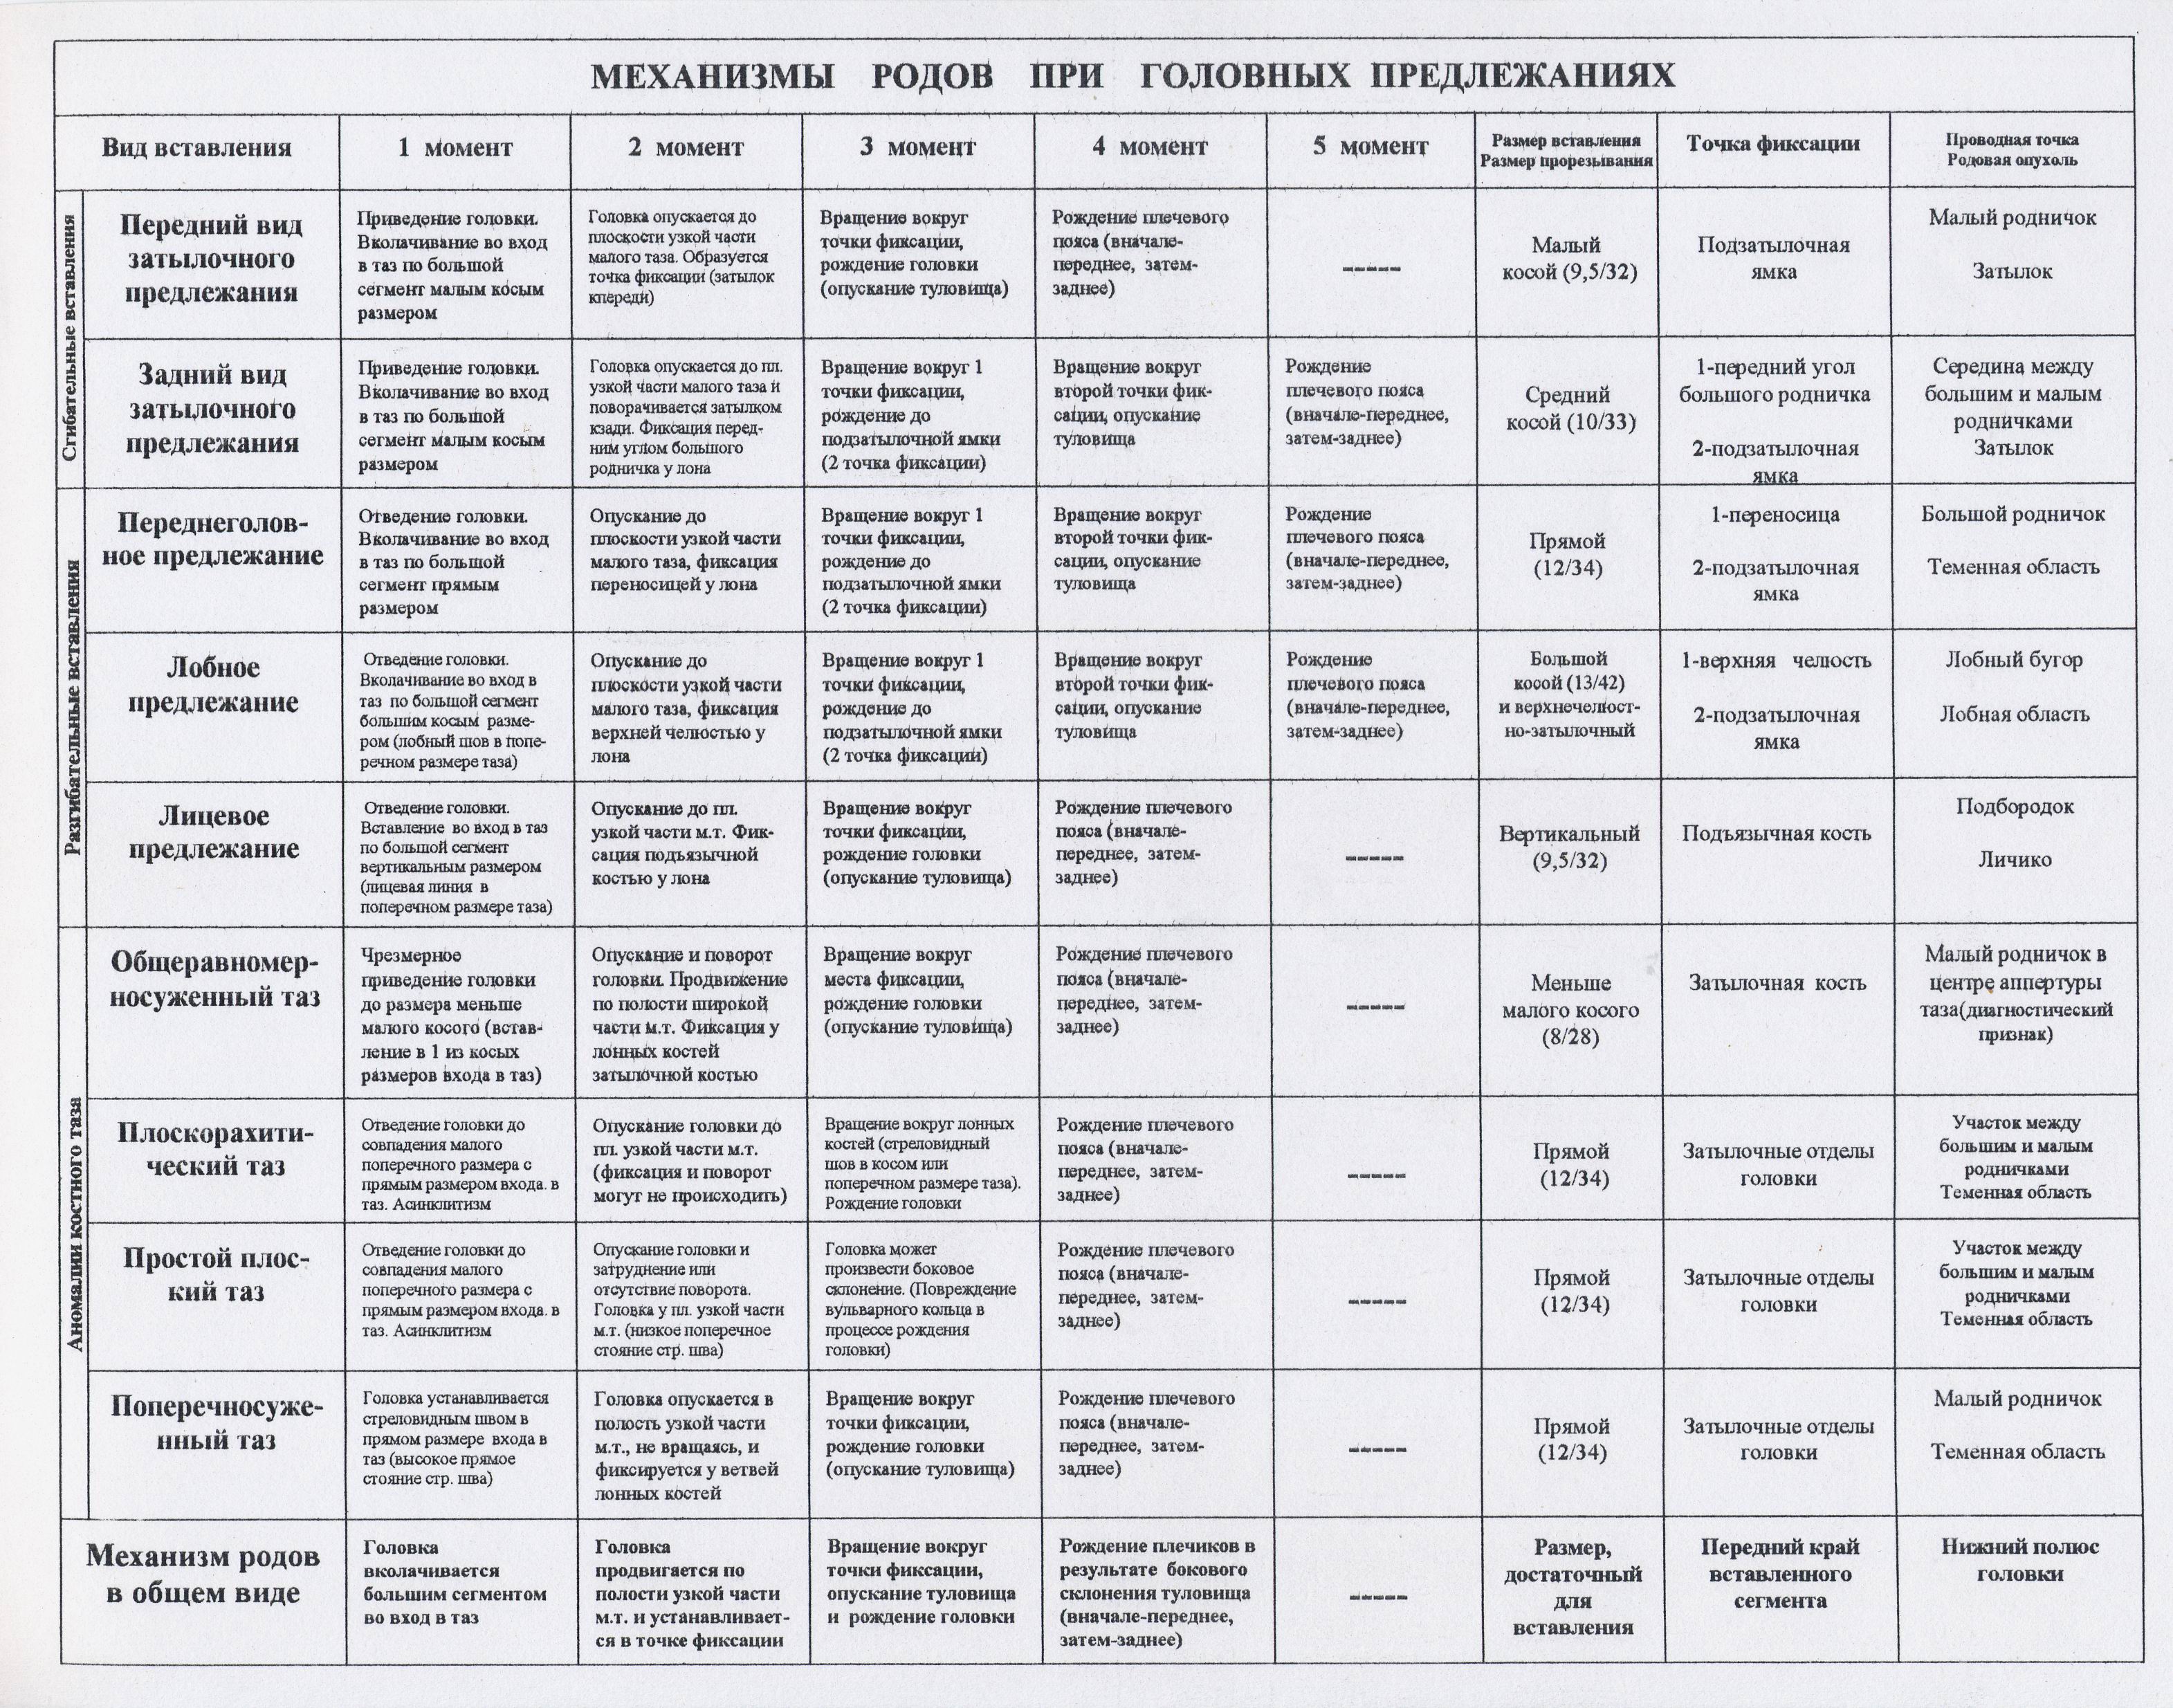

Биомеханизм родов таблица

Биомеханизм родов таблица